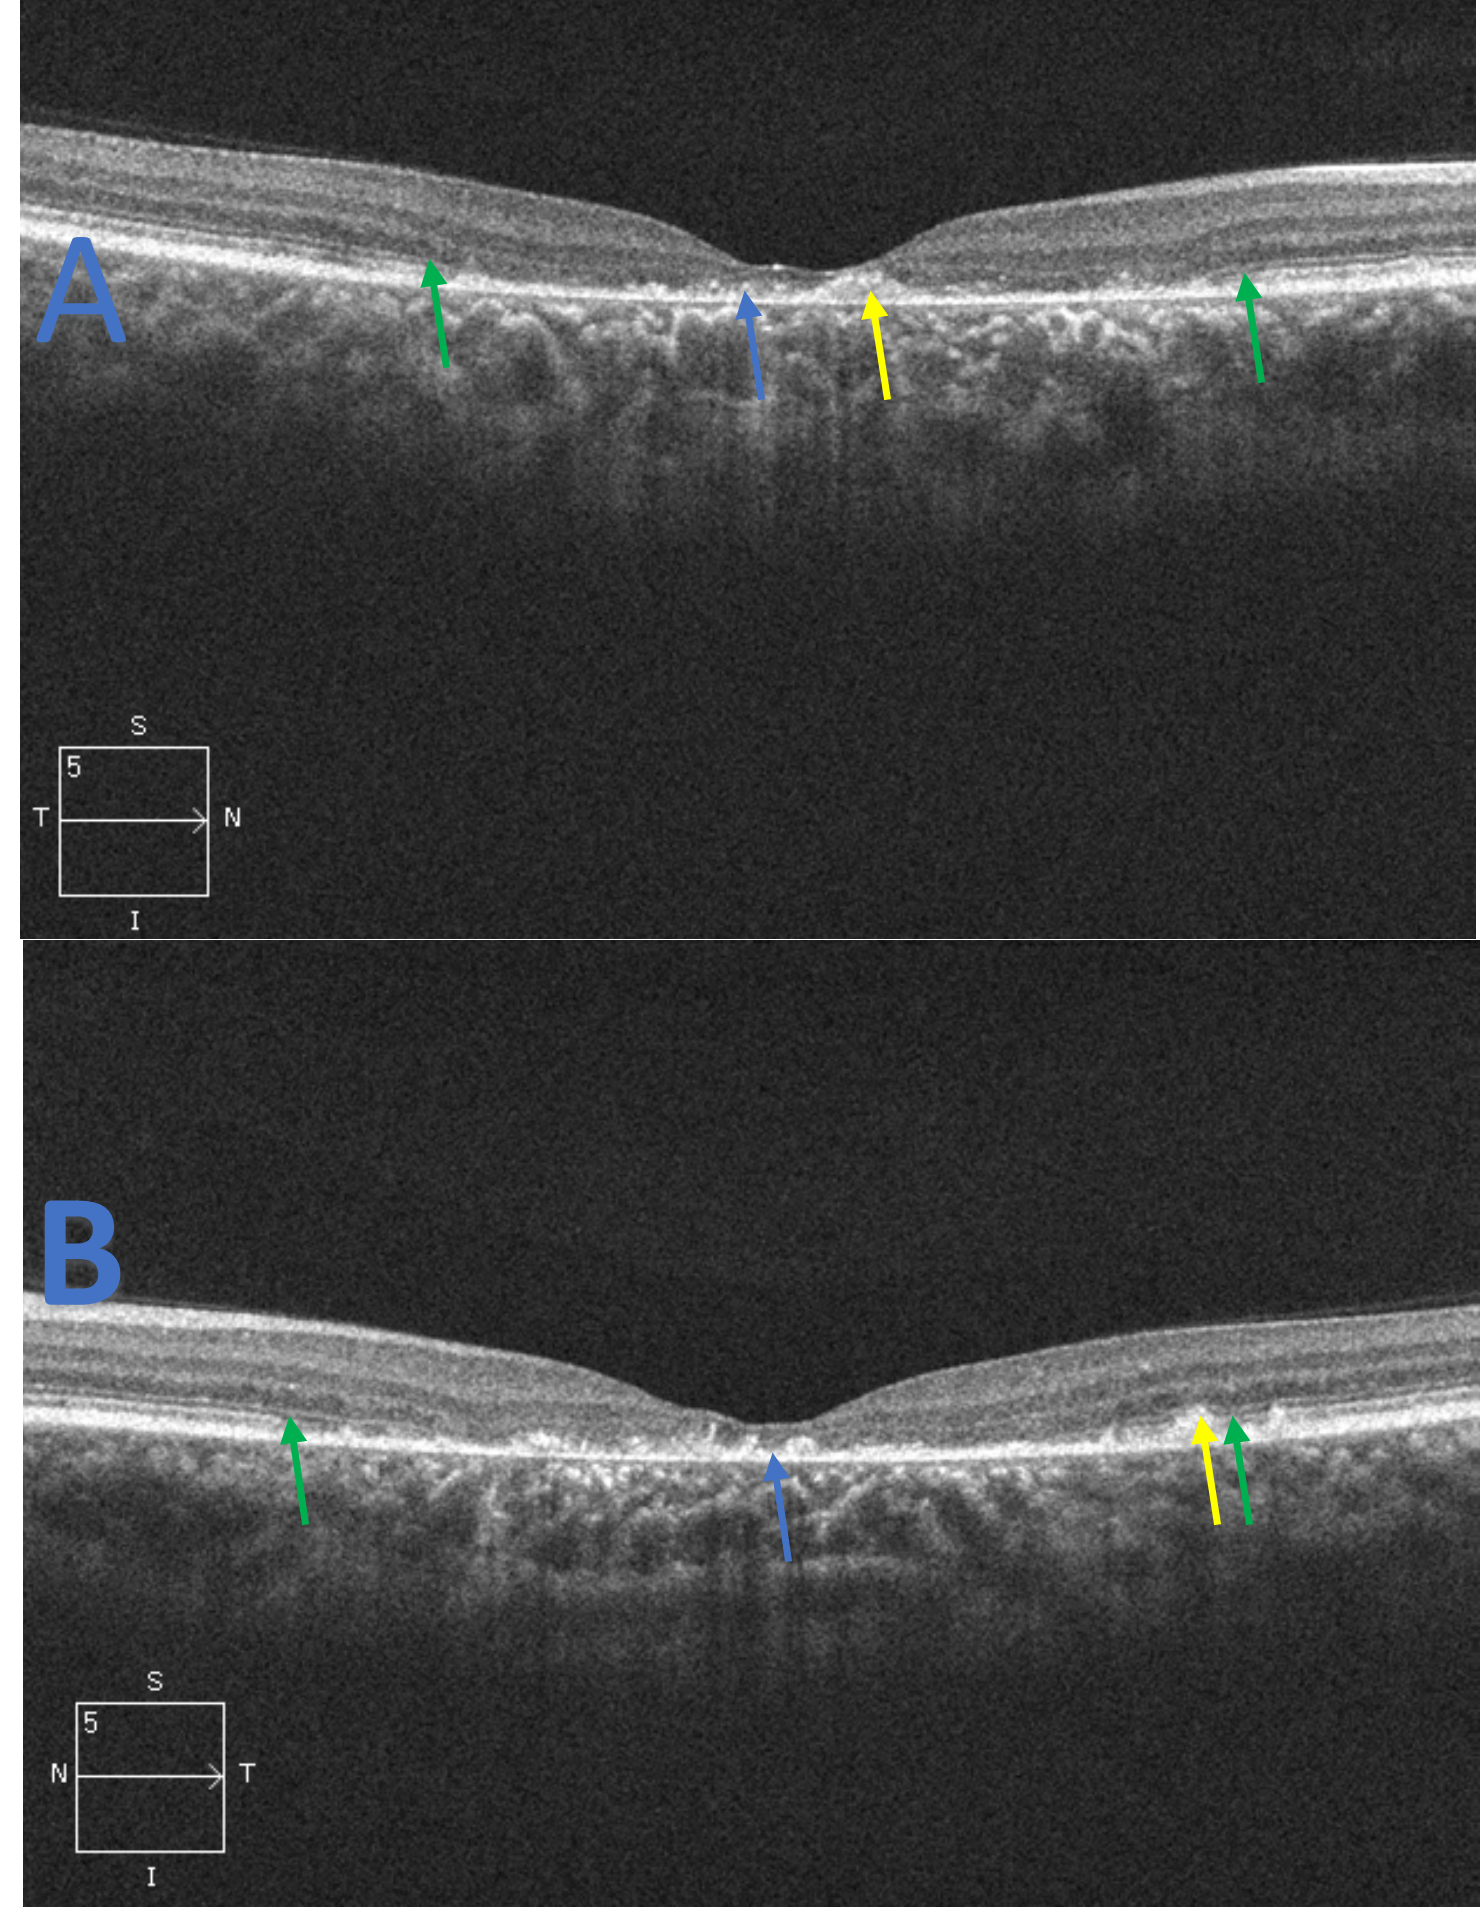

![]() Figure 2. Spectral domain optical coherence tomography raster scans of the macula, right eye (A) and left eye (B), for patient 1. The scans reveal central RPE atrophy (blue arrow) along with focal and hyper-reflective RPE thickening and disruption (yellow arrow). Foveal ellipsoid zone (EZ) atrophy is evident with extension nasal and temporal to the fovea in both eyes. The junction of the preserved and damaged EZ is indicated (green arrow). These findings correspond to the appearance of the fundus in Figure 1 and the central hypo-autofluorescence observed in Figure 3. Click to enlarge |

SD-OCT serves as a vital tool for assessing specific areas of retinal and choroidal involvement and for monitoring disease progression. The earliest known finding in children that has been imaged with OCT is external limiting membrane thickening.27,28 However, these patients may be asymptomatic at such a young age making its detection more difficult. As STGD1 is a disease of the outer retina, the inner retinal layers will be spared thus typical findings include damage and disruption to the macular outer retina layers including the EZ and the RPE. As the condition progresses, total atrophy of the layers will occur with preservation of the more peripheral macular tissue. These findings were seen in both patients as patient 1 had central EZ loss with accompanying RPE atrophy. Her peripheral retina was spared of any damage. Patient 2 had more mild initial findings as seen with foveal EZ and RPE disruption. However, this eventually transitioned to more EZ and RPE involvement and vision loss. This correlates to the typical bull’s eye maculopathy appearance that is associated with STGD1. As almost all commercially available SD-OCT instruments have progression software, clinicians can use specific parameters such as total retinal thickness, macular volume and outer retinal thickness to monitor progression.1 Although not needed to diagnose or monitor the condition, newer types of OCT, such as enhanced depth OCT and swept source OCT, can be used to visualize and image the choroid and its possible role in STGD1. Researchers have described four choroidal patterns that correlate with the loss of retinal structures and retinal integrity: stage 1 represents a normal choroid; stage 2 represents a reduced Sattler or Haller layer; stage 3 represents a reduced Sattler and Haller layer; stage 4 represents reduced Sattler and Haller layers with choroidal caverns.4 Currently, investigators are unsure why these caverns form. Enhanced depth imaging was not performed in either patient involved in this case report. However, based on the appearance of the choroid on the available SD-OCT scans, patient 1 likely had stage 2 choroidal involvement with a reduced Sattler layer while patient 2 likely had stage 3 choroidal involvement.